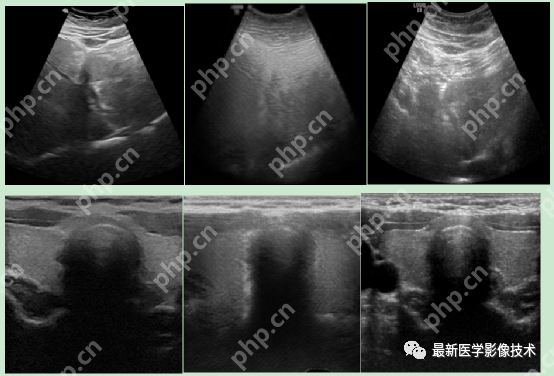

6、测试集部分生成结果

左图为低质量图像,右图为生成的高质量图像。